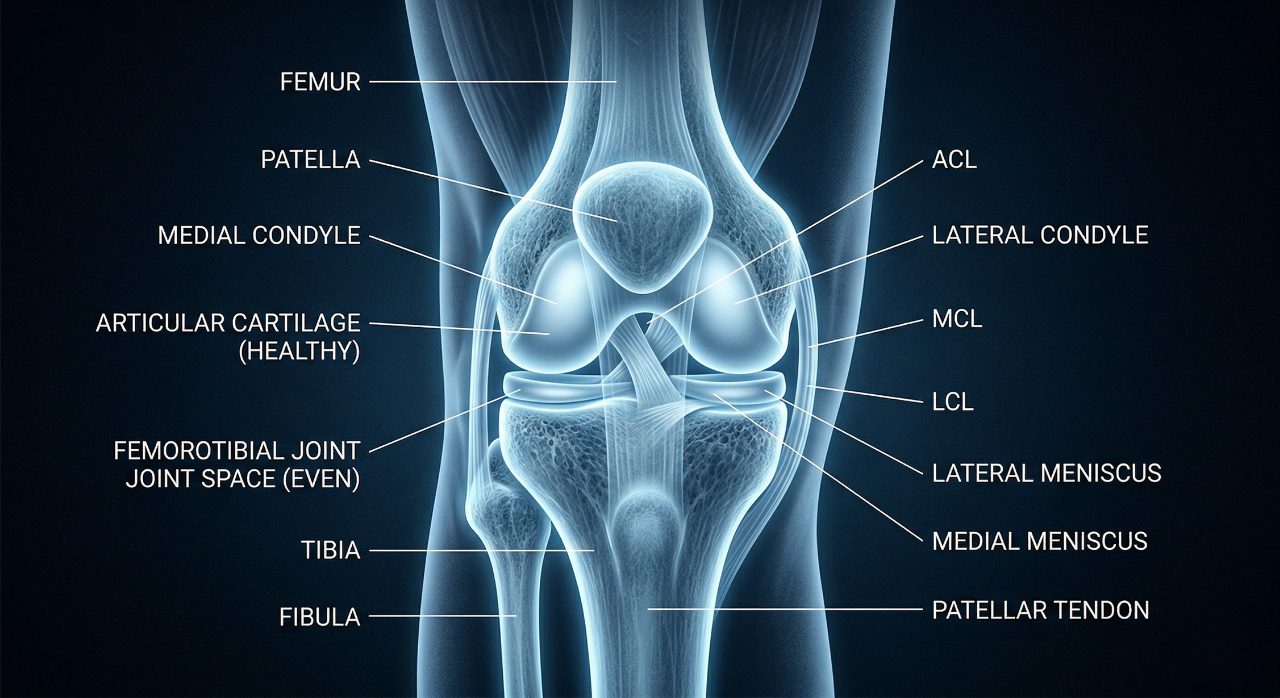

Glucosamine is an amino sugar — a molecule combining a sugar (glucose) with an amino group — that functions as a metabolic precursor for glycosaminoglycans (GAGs). Glycosaminoglycans are long-chain polysaccharide molecules that form the structural backbone of articular cartilage, synovial fluid, tendons, ligaments, and other connective tissues throughout the musculoskeletal system.

In articular cartilage specifically, glycosaminoglycans — primarily chondroitin sulphate and keratan sulphate — are attached to core proteins to form proteoglycans. These proteoglycan molecules are embedded within a type II collagen framework to create the unique viscoelastic properties of cartilage: the ability to absorb compressive load and return to shape, maintain hydration, and distribute mechanical stress across the joint surface. The integrity of this proteoglycan network is what gives healthy cartilage its shock-absorbing capacity.

In healthy joints, glucosamine is synthesised endogenously from glucose and glutamine through the hexosamine biosynthesis pathway in chondrocytes (cartilage cells). As joints age, chondrocyte metabolic activity declines, and the balance between cartilage matrix synthesis and matrix degradation shifts gradually toward net degradation. In osteoarthritis, pro-inflammatory cytokines (TNF-α, IL-1β) further suppress chondrocyte anabolic activity while upregulating the production of matrix-degrading enzymes (MMPs, aggrecanases). The result is progressive loss of proteoglycan content and cartilage volume — the structural changes visible on X-ray as joint space narrowing.

The rationale for glucosamine supplementation is that providing exogenous glucosamine substrate may support endogenous glycosaminoglycan synthesis in ageing chondrocytes, potentially helping to maintain cartilage matrix composition and slow the net degradation that characterises OA progression.